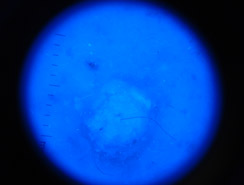

Dermatoscopia

Lo studio e la diagnosi delle neoformazioni cutanee attraverso strumenti specifici indicati per un'analisi delle caratteristiche strutturali superficiali e profonde delle varie neoformazioni cutanee: dermatoscopia, dermalite a luci fotocromatiche, mappatura nevica con videodermatoscopia digitale.